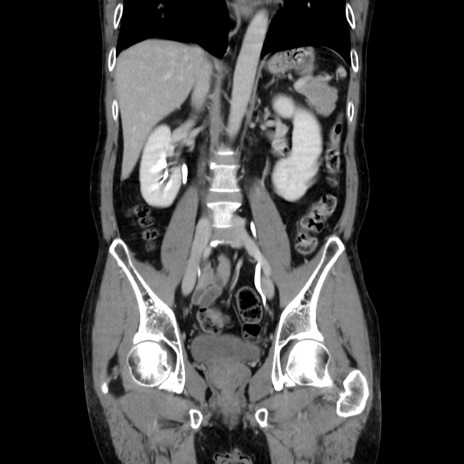

症例37(冠状断像)

【症例】40歳代 男性

【主訴】腹痛

【現病歴】4時間ほど前に電車に乗車中に臍部上より腹痛出現。徐々に増悪し起立困難となり、救急外来受診。生ものは数日食べていない。今朝お雑煮を食べた。

【身体所見】BT 36.8℃、BP 117/84mmHg、HR 91/min、SpO2 97%、苦悶様、腹部:臍上部広範囲圧痛あり、反跳痛±

【データ】WBC 8100、CRP 0.03